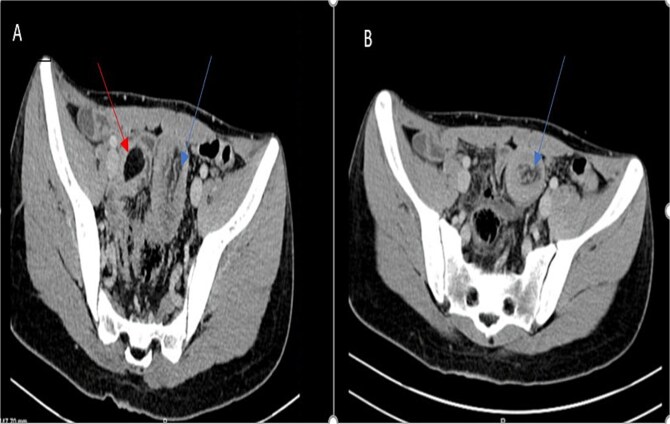

肠套叠是一种罕见的成人小肠梗阻的原因,通常与恶性病变有关,但偶尔由良性病因如脂肪瘤引起。临床表现多样,症状从腹痛到排便习惯改变。计算机断层扫描在诊断中起着关键作用。手术干预仍然是治疗的基石,包括切除受影响的肠段和去除潜在的病变。本病例报告报告了一例27岁男性空肠脂肪瘤引起的肠套叠的独特病例,重点介绍了其临床特征、诊断方法以及及时手术干预对患者最佳预后的关键作用。

Intussusception is a rare cause of adult small bowel obstruction, often associated with malignant lesions but occasionally caused by benign etiologies like lipomas. The clinical presentation is diverse, with symptoms ranging from abdominal pain to changes in bowel habits. Computed tomography plays a pivotal role in diagnosis. Surgical intervention remains the cornerstone of treatment, involving resection of the affected bowel segment and removal of underlying lesions. This case report presents a unique occurrence of intussusception caused by jejunal lipoma in a 27-year-old male, highlighting its clinical features, diagnostic approach, and the crucial role of timely surgical intervention for optimal patient outcomes.